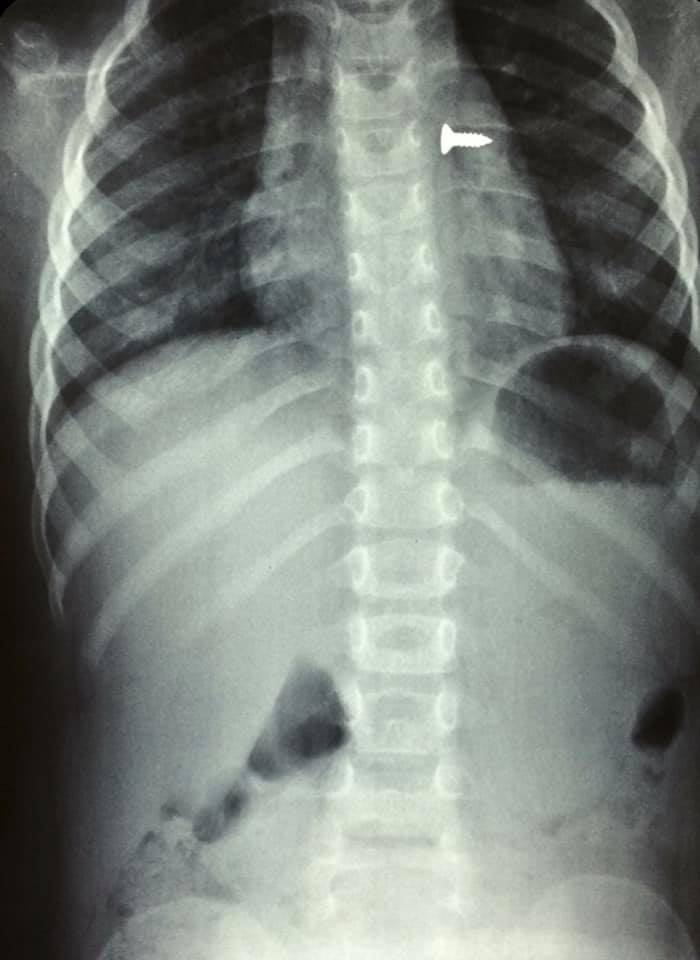

Αμέσως έβγαλε ακτινογραφίες, που έδειξαν πως η βίδα βρισκόταν στον αριστερό του πνεύμονα, με τις εικόνες να είναι σοκαριστικές.

Οι γιατροί οδήγησαν το κορίτσι στο χειρουργείο και μετά από αρκετή ώρα κατάφεραν να αφαιρέσουν την βίδα.

Ο κ. Προκοπάκης σε ανάρτησή του στα social media ανέφερε: «Πολύ επείγον χειρουργείο! Πριν από λίγο. Αφαίρεση βίδας από αριστερό βρογχικό δέντρο τρίχρονου κοριτσιού. Πολύ επικίνδυνο…».